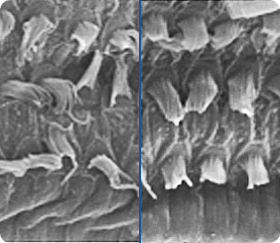

Mit den Fortschritten in Wissenschaft und Technik stellen sich die Forscher immer wieder die Frage, ob es möglich ist, ein Präparat herzustellen, das in der Lage ist, das Gewebe des Trommelfells und die Haarzellen der Cochlea zu erneuern. Denn die Zerstörung der Haarzellen führt zu einem teilweisen oder vollständigen Verlust des Hörvermögens - und ihre Wiederherstellung hat den Effekt, dass sich das Hörvermögen verbessert und die Schallwahrnehmung verbessert. Könnte die innovative Formulierung von AudioVerde eine Chance bieten, die Zellen auf natürliche Weise wiederherzustellen und das Hörvermögen von Menschen mit Hörminderung zu verbessern?

Haarzellen bei Hörstörungen und nach der Hörverbesserung. / Bewegen Sie den Schieberegler, um den Unterschied zu sehen.